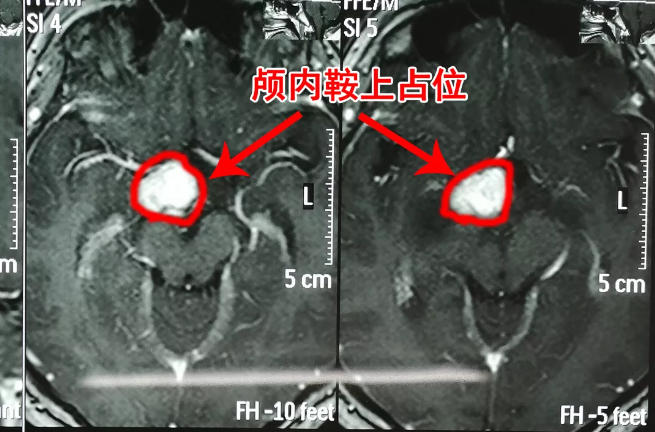

直到当地一位医生建议他们做头颅核磁共振检查后,王宁身上发生的症状才水落石出——颅内鞍上占位。

王宁的颅内鞍上占位,也就是在颅内鞍区上方存在占位,医生根据病史及影像资料初步考虑为生殖细胞瘤。但由于鞍区上方占位情况较复杂,只有拿到病理诊断这个医学诊断的“金标准”,才能针对性的开展下一步治疗。